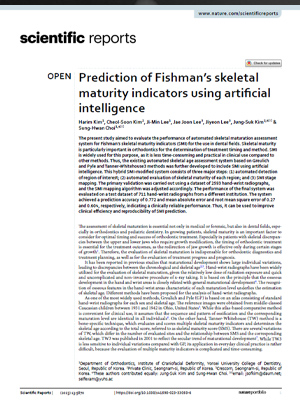

이지민 대표원장이 공동 연구한 AI 기반 성장판 분석 논문의 학술적 근거를 바탕으로,

정밀 성장판 검사 프로그램을 통해 성장기 아동의 성장 페이스를 정확히 예측하고

최적의 교정 시기와 치료 계획을 설계합니다.

소아청소년기의 정상적인 성장 여부 판단을 위해

손뼈 엑스레이를 분석하여

높은 정확도의 골연령 판독 결과를 제시합니다.

엑스레이 판독 결과와 키와 몸무게 등의

환자 정보를 함께 평가하여 환자의 예상 신장을 비롯한

유용한 성장 정보를 담은 리포트를 제공합니다.